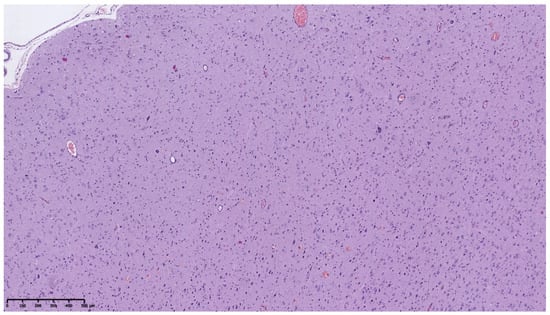

3.1. Clinical and Pathology Report